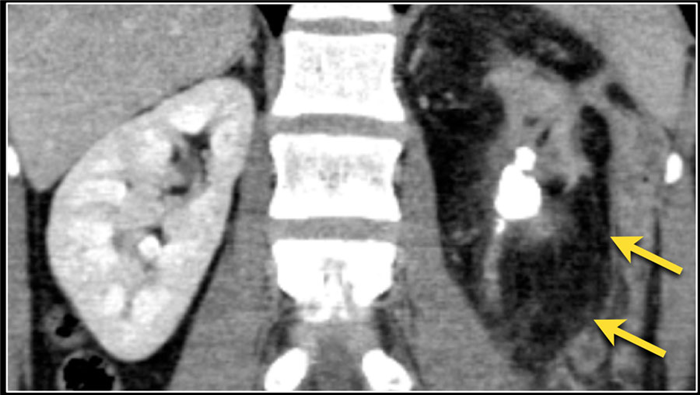

(Слева) КТ с контрастированием, коронарная проекция: у женщины 32 лет, поступившей с болью в боку, лихорадкой и позитивным бактериальным посевом крови на Е. coli, выявлены гематогенные стафилококковые абсцессы левой почки и левой поясничной мышцы.

(Справа) КТ с контрастированием, аксиальная проекция: у этой же пациентки визуализирован чрескожный дренажный катетер внутри абсцесса почки. После дренирования отмечено полное восстановление.